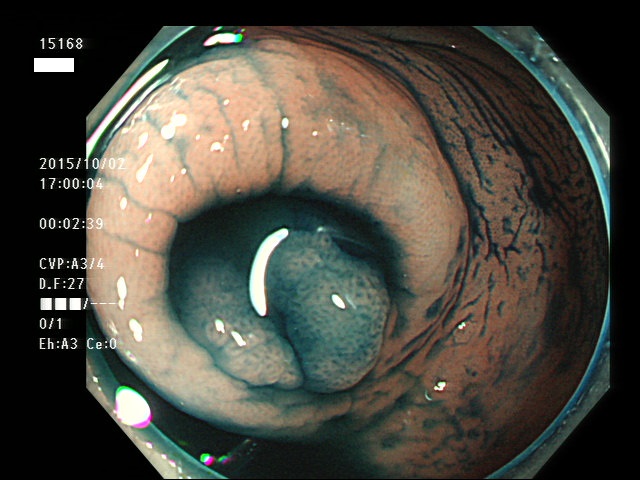

虫垂開口部の過形成ポリープ(SSAP)の例